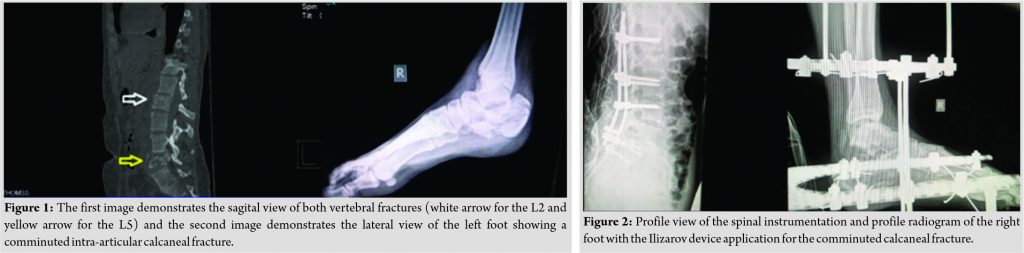

A 23-year-old female patient was admitted to the authors’ emergency department after falling from a height of 5 m. She complained of severe pain in her lumbar spine and right foot. She had no head trauma and the Glasgow coma score (GCS) was 15/15. Based on these findings, no brain computed tomography (CT) scan was performed at the emergency department after neurosurgeon’s consultation. Physical examination revealed paresis of L5 left root with significant weakness (1/5) of the left long toe extensor muscle and impaired light touch and pinprick sensation (both 1/2). Urinary retention was diagnosed by means of urinary bladder ultrasound and the anal sphincter was spoiled with associated perianal hypoesthesia. Radiograms and CT revealed an A3/AO type fracture of the second lumbar vertebra, a B1/AO-type fracture of the fifth lumbar vertebra, and a comminuted (sanders type 4) right calcaneal fracture (Fig. 1). Thirty hours after the initial admission at the emergency department a posterior minimal stabilization from L1 to S2 vertebrae accompanied by L5 decompression was performed to address the spinal fractures, while an Ilizarov device was applied to reduce and temporarily stabilize the calcaneal fracture (Fig. 2).